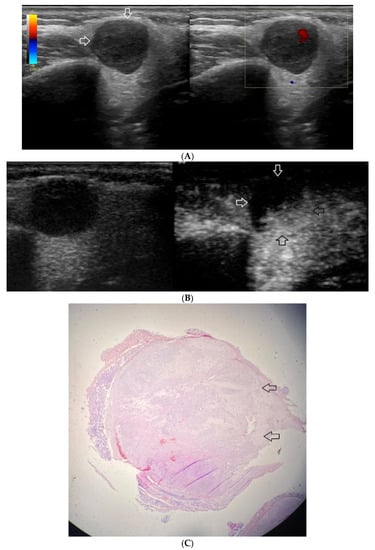

Figure 1.

(A−C) Lymphoepithelial carcinoma. (A) Routine ultrasonographic examination in B presentation and colour Doppler (CD): a hypoechogenic focal lesion of a heterogeneous echostructure (white arrows). On CD, low blood flow is observed. (B) Contrast-enhanced imaging in arterial phase: a strong heterogeneous enhancement of a lesion containing minor oval areas with no enhancement (white arrows). (C) Pathomorphological image, immunohistochemistry for CD3+. Aggregations of carcinomatous cells (white arrows) surrounded by scattered lymphoid tissue cells.